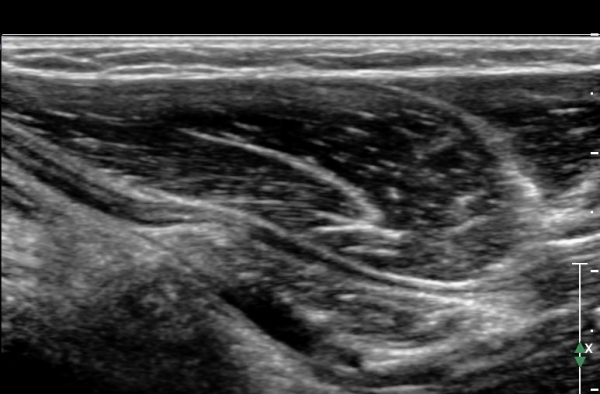

Á¤Á߽Űæ Á¾´Ü¸é°Ë»ç¿¡¼ ȸ³»±Ù ¿ä°ñµÎ ±â½ÃºÎ¿¡¼ Á¤Á߽ŰæÀÇ ±¹¼ÒÀû ¾Ð¹Ú°ú Ç¥ÃþÀ¸·Î ÀüÀ§°¡ °üÂûµÇ°í ¾Ð¹ÚÀÇ ±ÙÀ§ºÎ¿¡¼´Â Á¤Áß½Å°æ ºÎÁ¾ÀÌ °üÂûµÊ(»çÁö 3). ÀÌ·± º¯È´Â °ÇÃø(»çÁø 6)°ú ºñ±³ÇÏ¸ç ¶Ñ·ÇÇÔ.